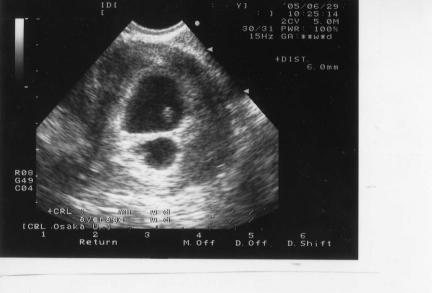

21日 胎嚢が2つある

29日 もも心拍確認(とまはまだ「このまま駄目かもしれない」とのお言葉。かなりショックを受けた。)